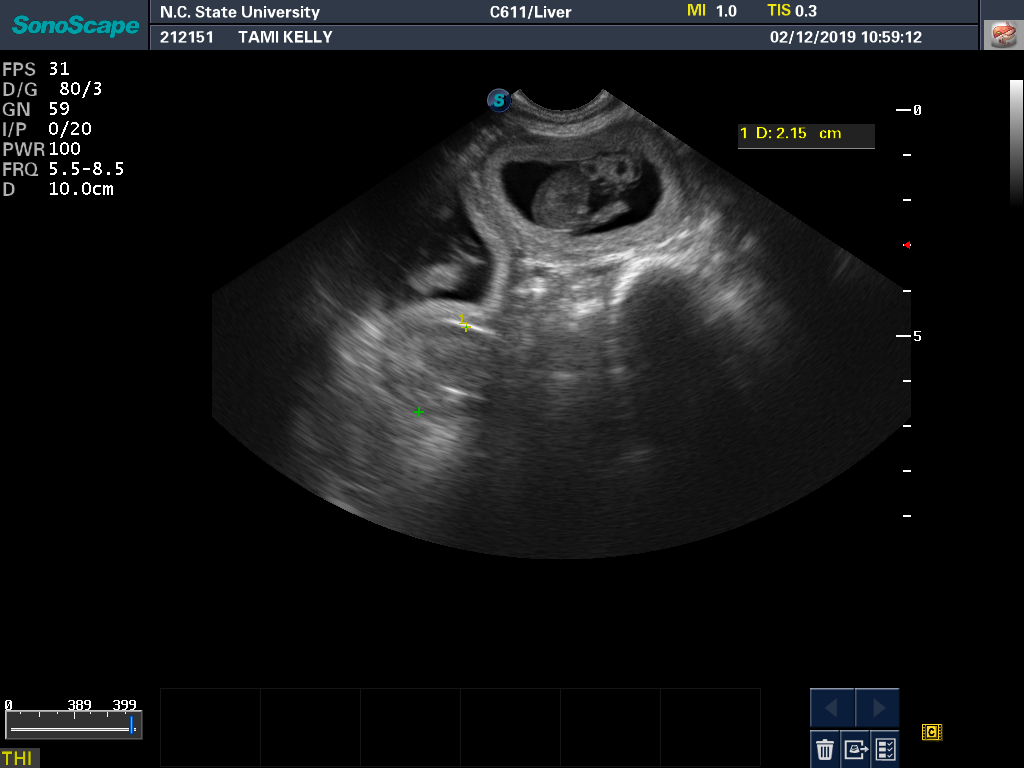

12 Feb

Tami had another ultrasound and progesterone check. All looks well. Here is a a good view of one of the puppies from the ultrasound monitor. And a view showing that there really are three puppies.